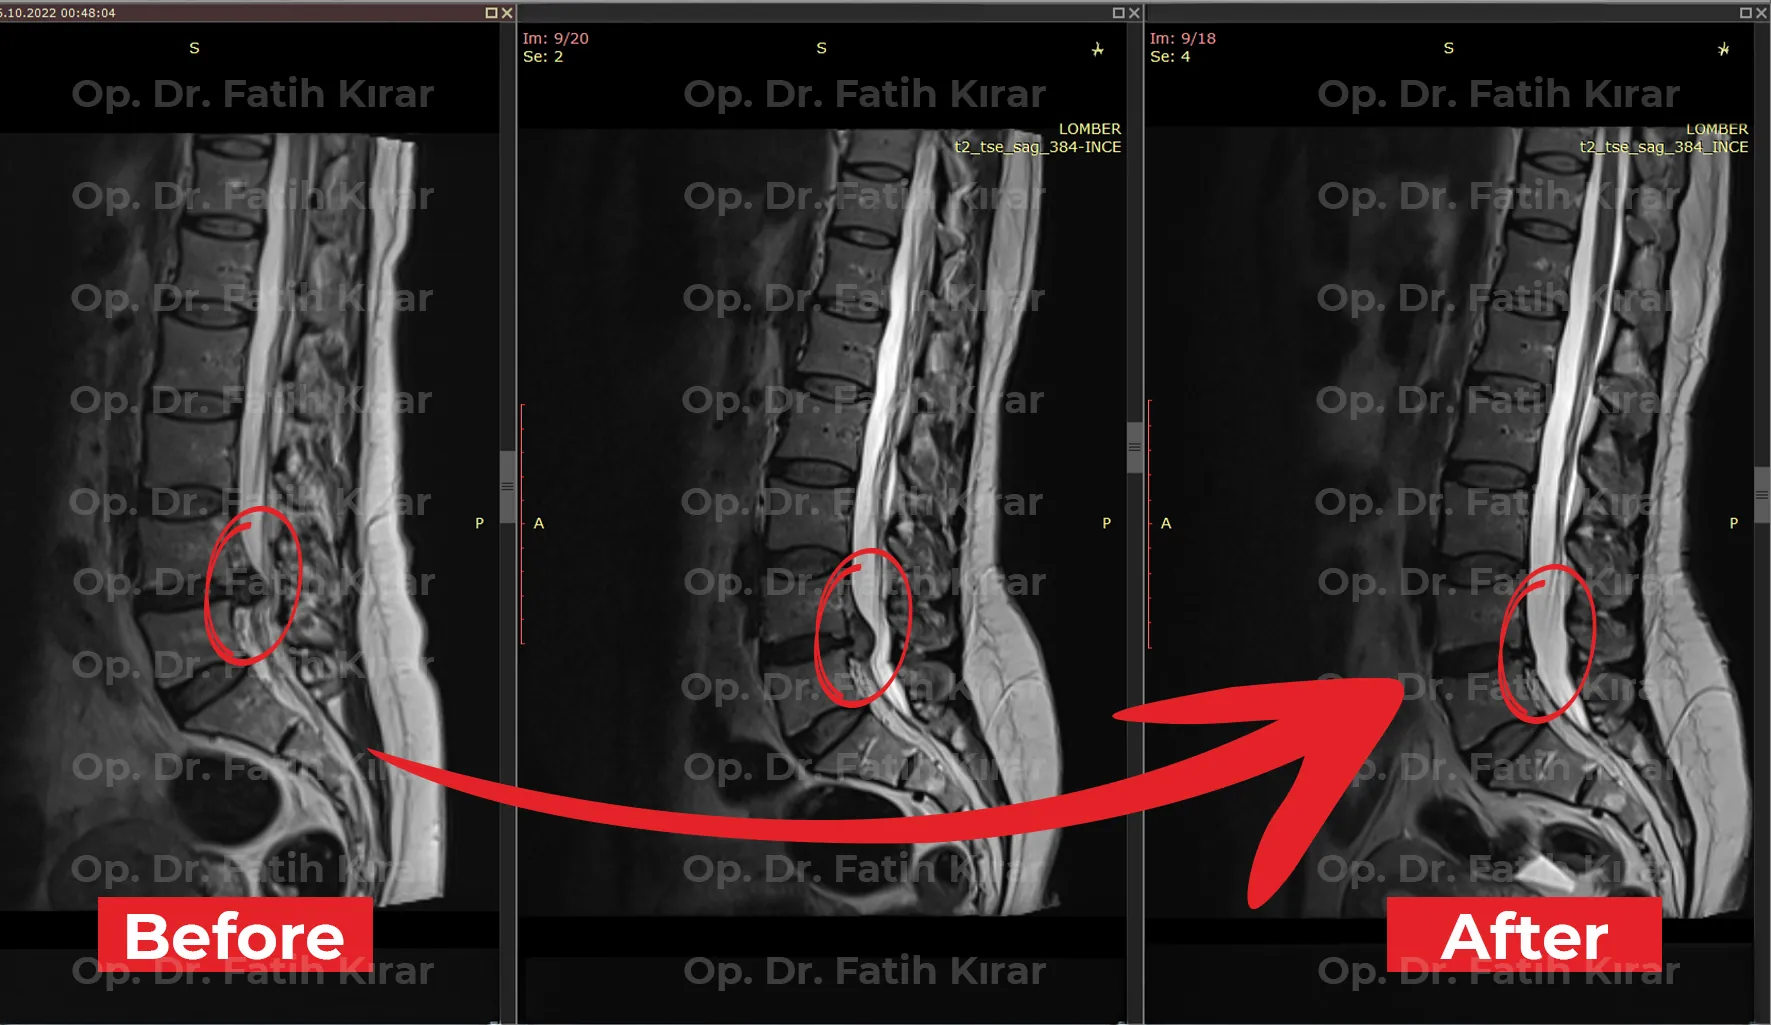

Gelişmiş fıtık tedavi sonuçlarımızdan gerçek önce ve sonra görüntüleri